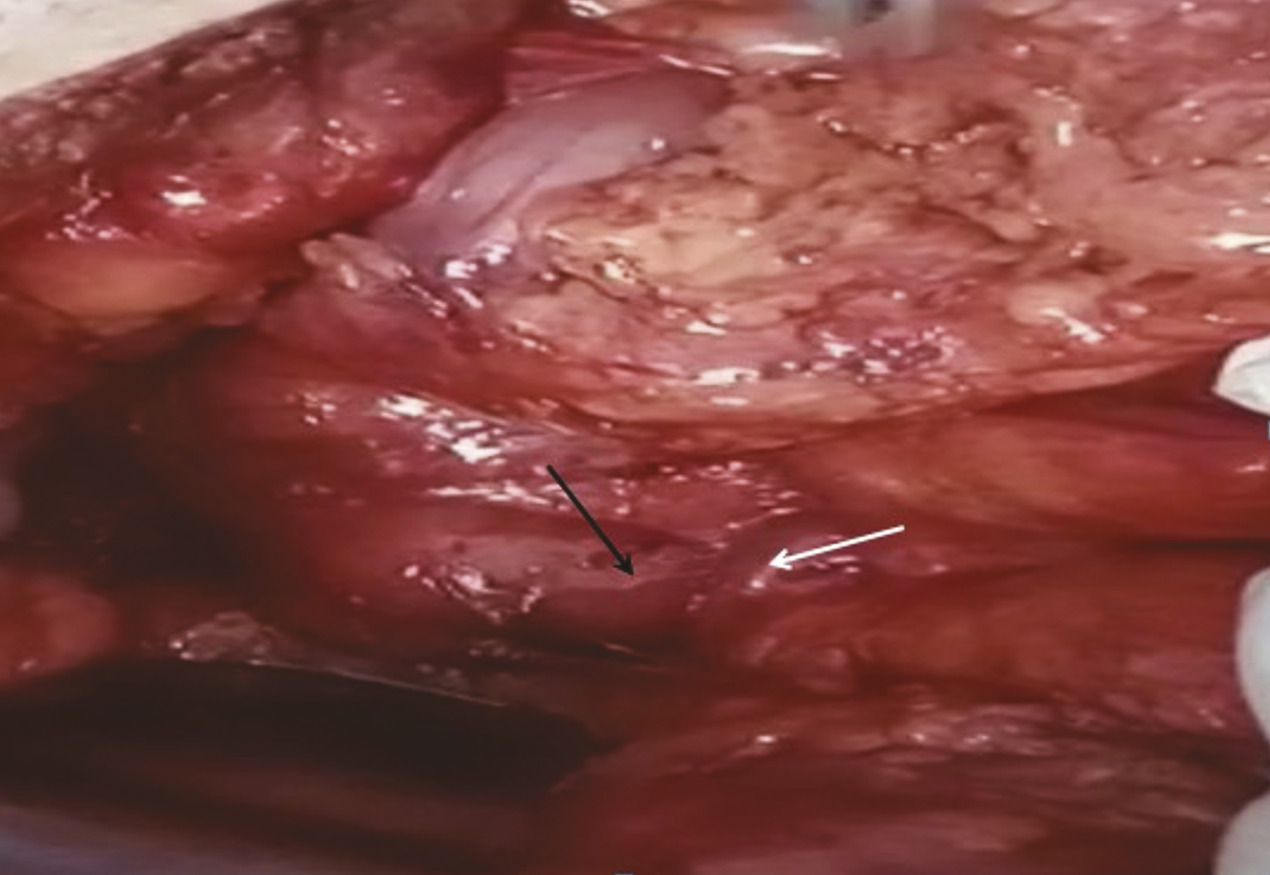

Le traitement médical initial a associé la mise en place d’une sonde nasogastrique et l’administration de solutions hydroélectrolytiques et métaboliques par voie parentérale. Cependant, après quinze jours de traitement, aucune amélioration clinique significative n’a été observée, la sonde gastrique a continué à drainer en moyenne 1 300 mL par jour. Face à cette situation, une intervention chirurgicale a été décidée. Lors de l’exploration chirurgicale réalisée par une incision médiane, une distension importante de l’estomac et du duodénum en amont de l’empreinte de l’artère mésentérique supérieure a été constatée ; en aval de cette empreinte, les anses grêles étaient aplaties (fig. 3 ). Une anastomose gastrojéjunale transmésocolique a été effectuée. Les suites postopératoires ont été normales. Les contrôles à un mois et à trois mois ont montré une nette amélioration des symptômes.

Le traitement médical initial a associé la mise en place d’une sonde nasogastrique et l’administration de solutions hydroélectrolytiques et métaboliques par voie parentérale. Cependant, après quinze jours de traitement, aucune amélioration clinique significative n’a été observée, la sonde gastrique a continué à drainer en moyenne 1 300 mL par jour. Face à cette situation, une intervention chirurgicale a été décidée. Lors de l’exploration chirurgicale réalisée par une incision médiane, une distension importante de l’estomac et du duodénum en amont de l’empreinte de l’artère mésentérique supérieure a été constatée ; en aval de cette empreinte, les anses grêles étaient aplaties (